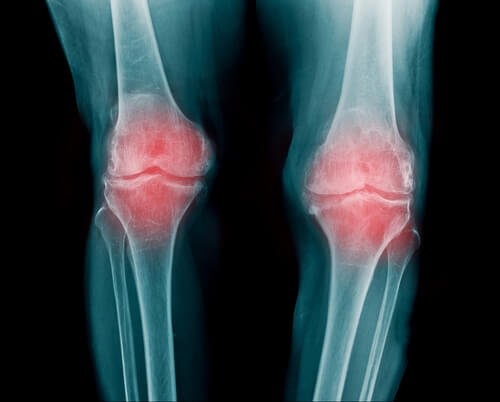

- Reumatoid arthritis er en betændelse i dine led. Det kan påvirke flere forskellige led ad gangen. Generelt ses det i fingre, arme og knæ.

- Personer med reumatoid arthritis vil opleve nedsat mobilitet. Efter den prikkende fornemmelse, begynder værre smerter oftest over tid.

- Dette sker i takt med at kalciumaflejringer ophobes i leddene. I begyndelsen kommer den prikkende følelse, men i det at brusken svækkes og gradvist nedbrydes, vil det forårsage en smerte der kun vil blive værre over tid.

- Man ser oftest reumatoid arthritis i håndled, fingre og knæ. Det kan dog også påvirke andre led. Denne sygdom er forbundet med slidgigt og andre lidelser relateret til skjoldbruskkirtlen.

- Det er en smertefuld sygdom, men den ødelægger ikke leddet.